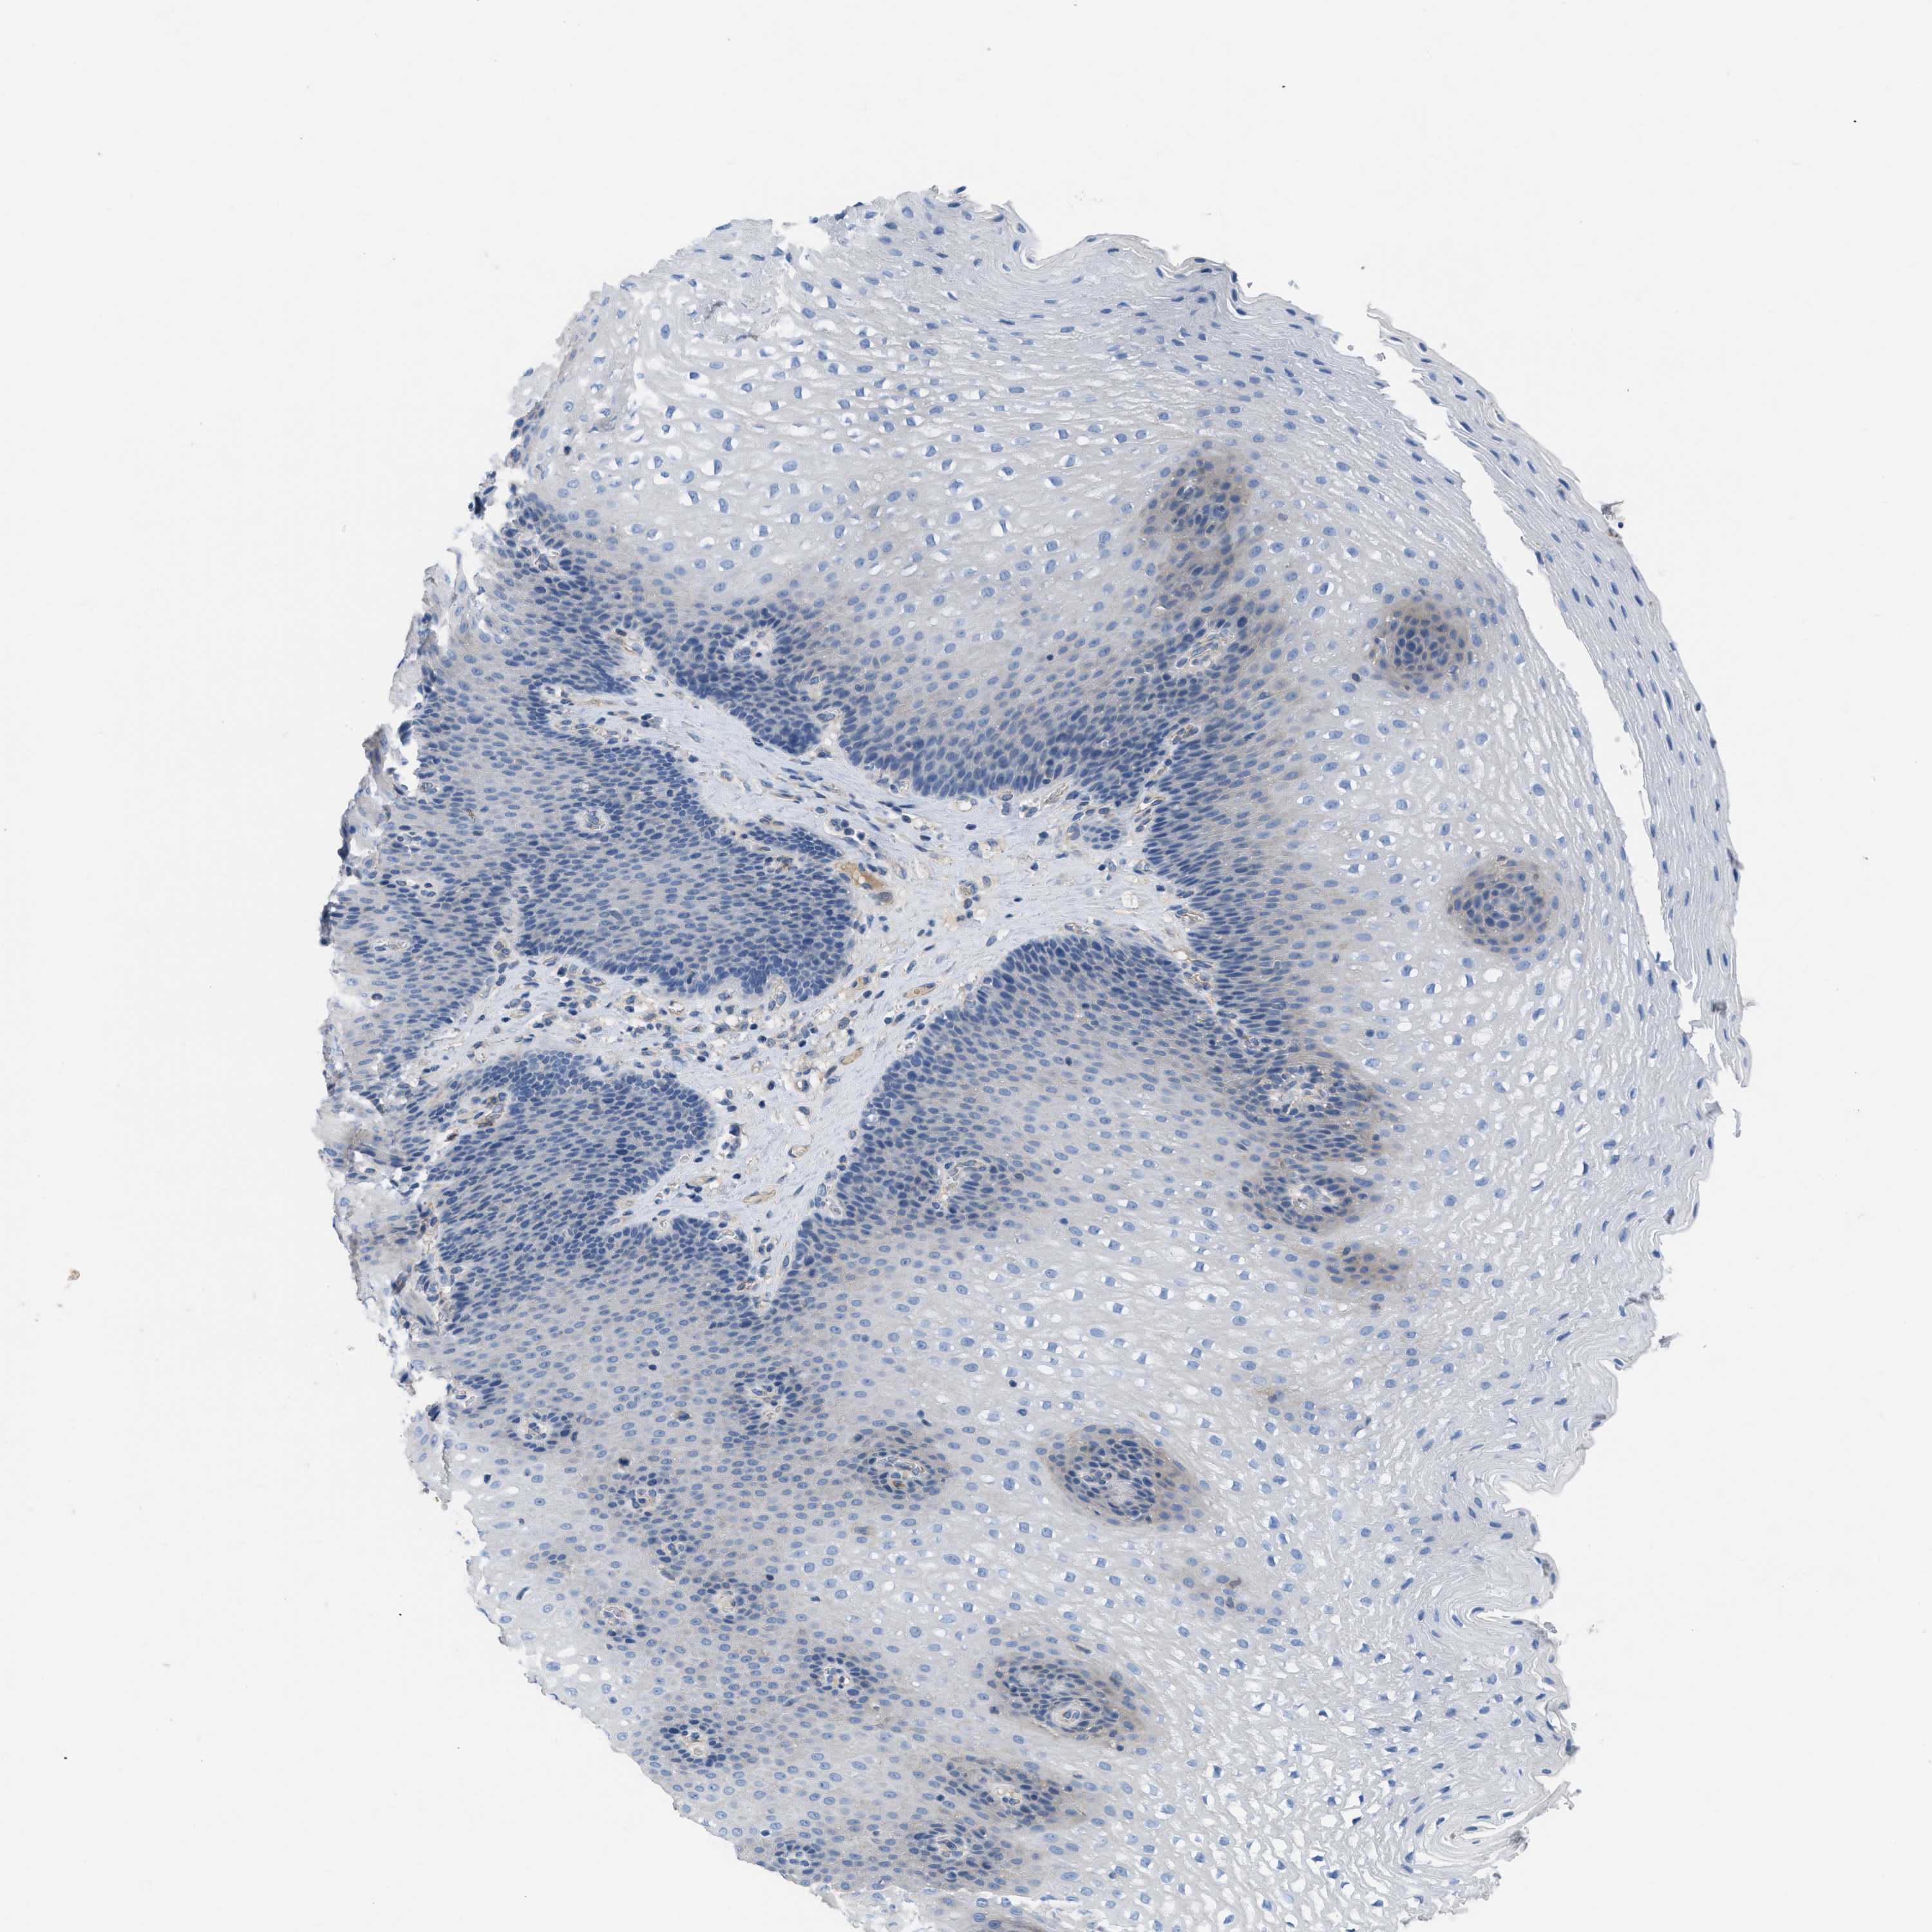

Antibody HPA013835

Squamous epithelial cells Not detected